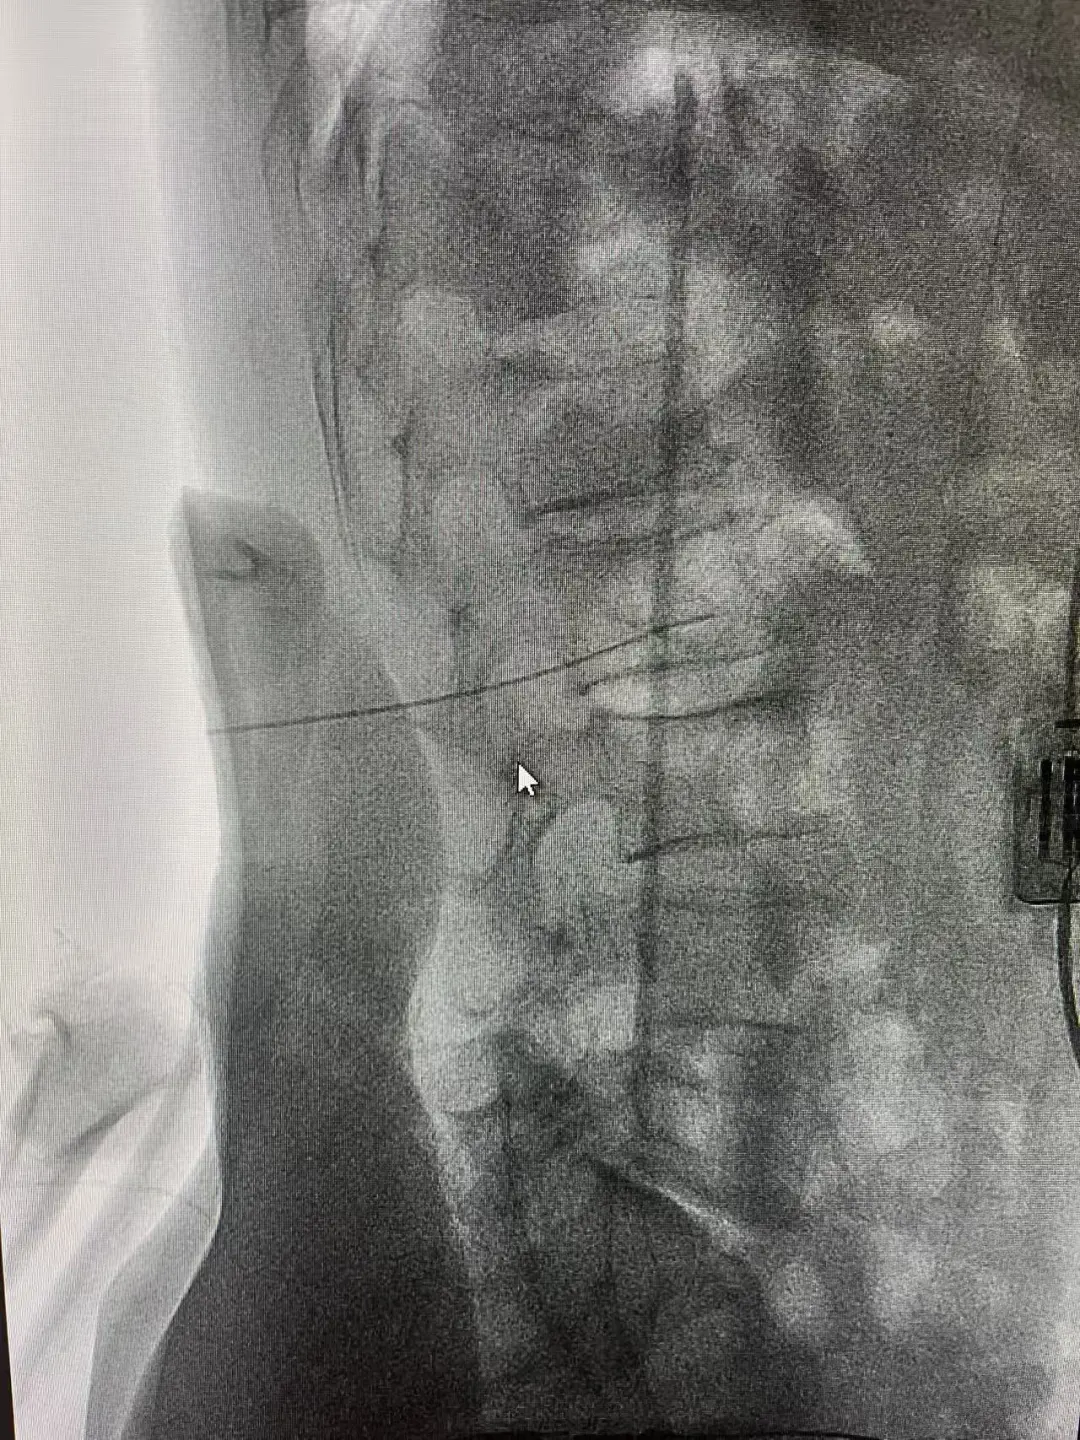

手术在DSA室精准开展:团队以C臂及影像学检查定位腰2-3交感神经节,避开周围脏器血管,将射频消融针置入目标区域,在安全温度下完成神经消融;随后经股动脉穿刺建立通路,导丝顺利通过闭塞段,采用长球囊低压扩张重建血管管腔。术中造影显示,闭塞血管成功开通,血流直达足部,患者即时感觉疼痛缓解,足背皮温升高。